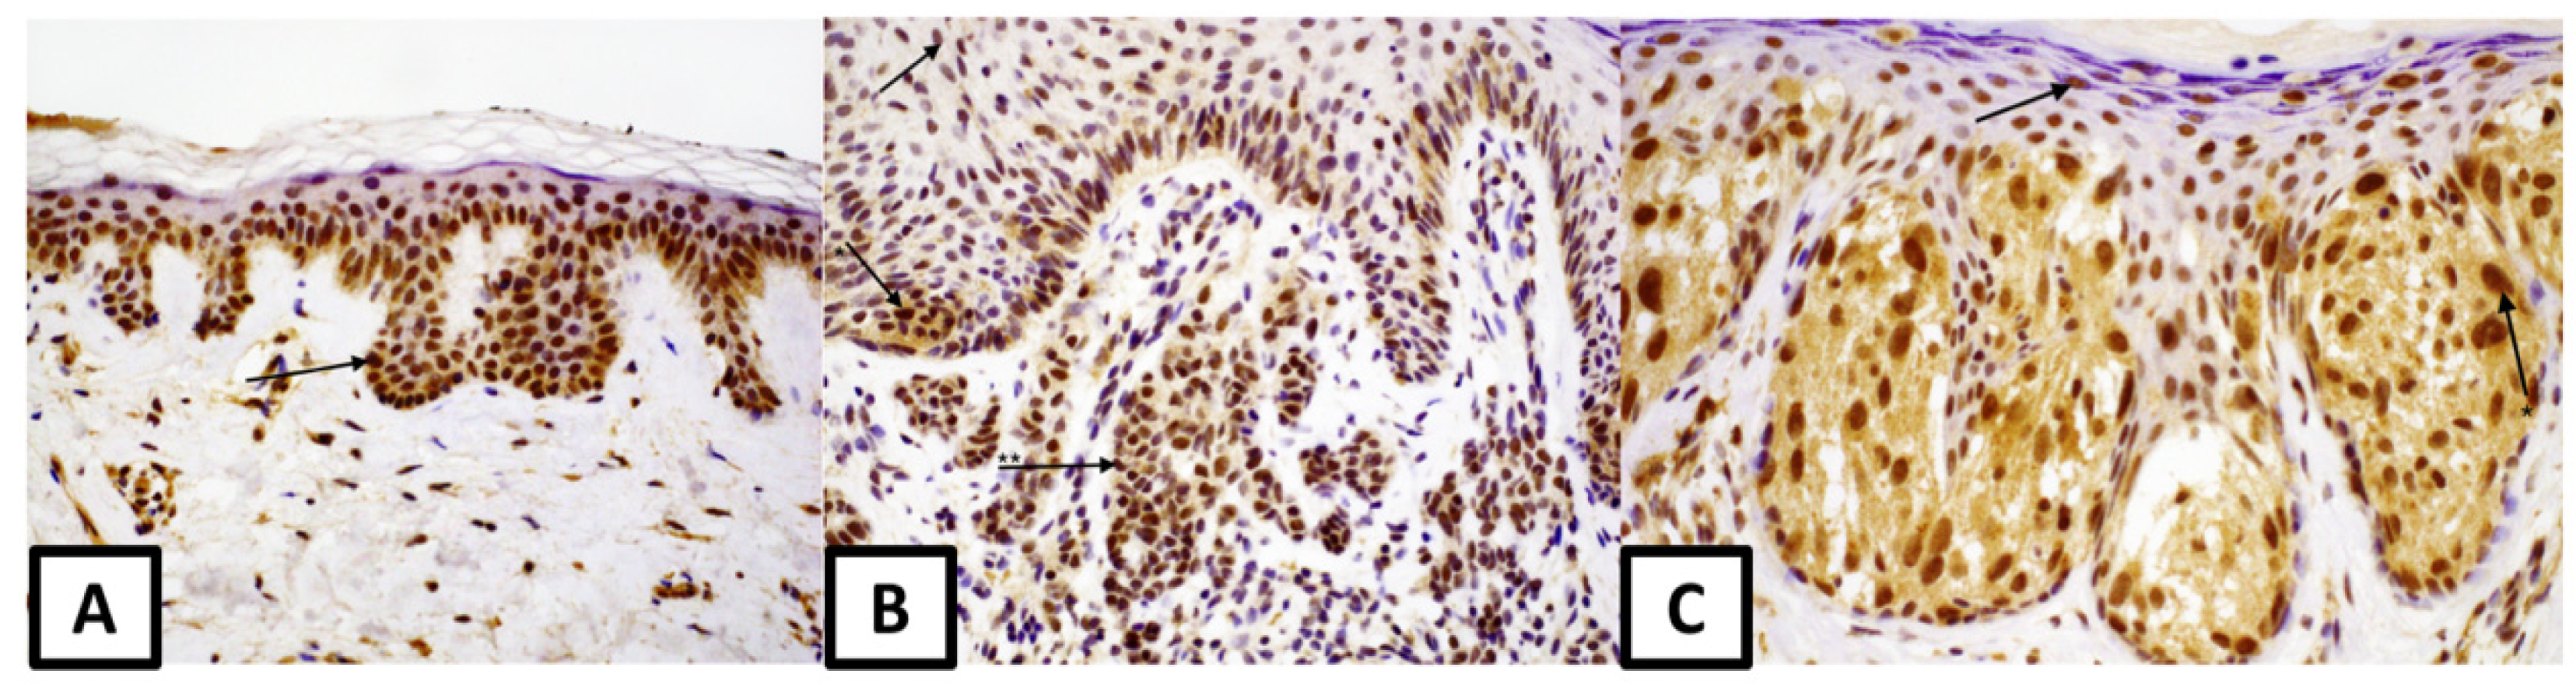

3. Results